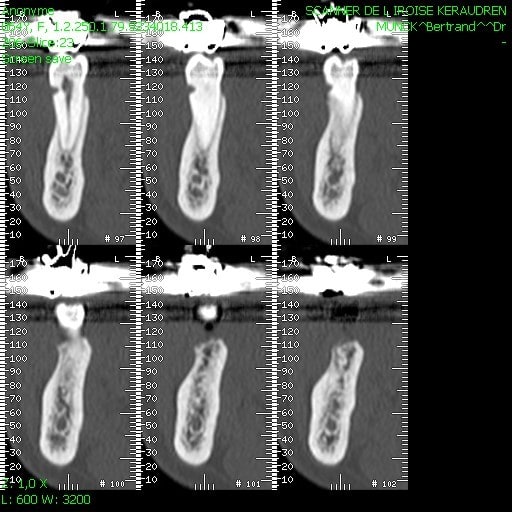

sous réserves bien sur il me semble que coupe 108/109/110 il reste l'os interradiculaire.

alors soit un carottage dedans et tu te sers de la carotte pour combler en distal et mesial. (cf Céramik je crois)

soit expansion condensation du septum interadiculaire

il semble que les zones d'extraction commencent à se reminéraliser. Recherches si possible un ancrage apicale et récupéres de l'os comme suggéré par carottage du septum avec une petite tréphine de diamètre compatible avec la taille de ton implant soit en récupérant l'os de forage avec un filtre récupérateur d'os. Il est fort probable qu'une partie vestibulaire de l'implant ne soit pas intra-osseux, tu places du bio-oss mélangé avec l'os récupéré sur la zone à régénérer et tu recouvres avec une membrane assez "rigide" type bio-mend extend éventuellement punaisée si besoin.